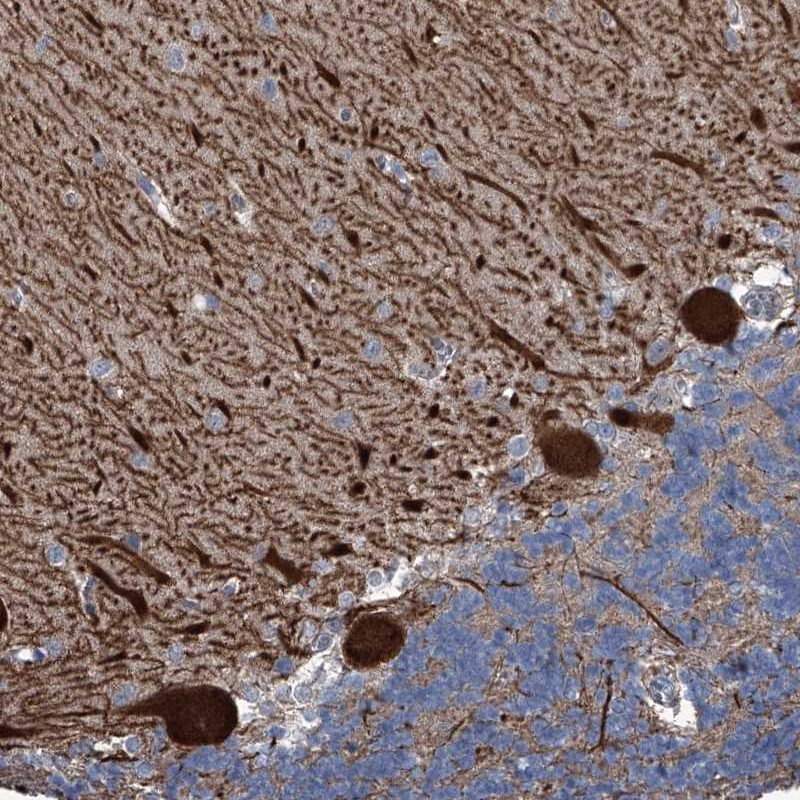

Immunohistochemical staining of human cerebellum shows strong cytoplasmic positivity in purkinje cells.